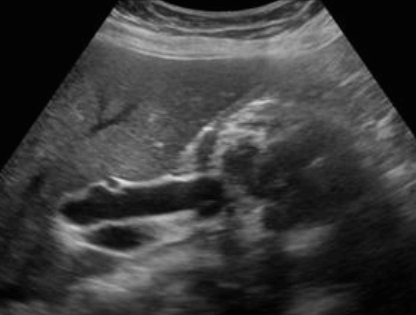

US finding

- 담낭관 또는 담낭 경부에 결석이 확인된다.

- 총간관(CHD) 또는 담낭관(cystic duct)의 확장소견이 보인다.

- 간내외 담관의 확장이 관찰된다.